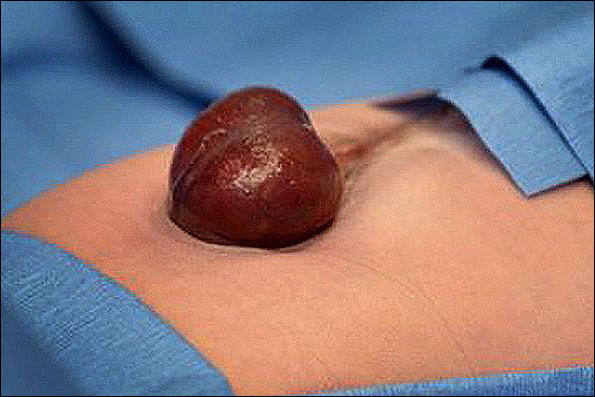

ادرینا کاردناس که در ماه اکتبر (مهرماه) متولد شده بود به یک بیماری نادر مادرزادی که از آن با عنوان " قلب بیرون از قفسه سینه" (ectopia cordis) یاد می شود، مبتلا است.

، ادرینا کاردناس که در ماه اکتبر (مهرماه) متولد شده بود به یک بیماری نادر مادرزادی که از آن با عنوان " قلب بیرون از قفسه سینه" (ectopia cordis) یاد می شود، مبتلا است.

پزشکان در چند هفته باقی مانده تا وضع حمل معاینات ویژه قلب و ام آر آی ویزه نوزادان دریافتند که یک سوم از قلب این نوزاد خارج از بدنش قرار دارد.

در 15 اکتبر، آدرینا از طریق سزارین متولد شد و روز پس از آن تحت جراحی قلب قرار گرفت.

دکتر لاری هولیر رئیس بخش جراحی پلاستیک اظهار داشت: وقتی که جراحان قلب کار خود را روز بدن آدرینا به پایان رساندند ، تیم جراحی پلاستیک نقش مهمی در تکمیل این جراحی ایفا کرد ، چرا که این گروه مسئول پوشاندن قلب وی در زیر پوست و ماهیچه ها بودند.